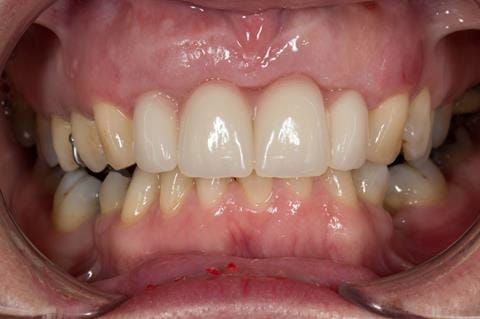

- High smile line showing gum above gingival zeniths of upper front teeth when smiling. Aesthetic failure of the upper four incisors with inflammation of the gingivae and mis-match of the gingival zenith levels.

- Other than the maxillary incisors the remaining dentition was in marginally better condition being moderately to heavily restored. Many will probably require replacement and restoration from time to time mainly from wear and tear owing to occlusal forces.

Following consultation and second discussion appointment the patient chose to have option 3 namely, a maxillary cobalt chromium based partial denture/protective occlusal splint. The clinical situation and treatment process is shown in detail below with photographs. The patient was successfully rehabilitated with this and her quality of life considerably improved. The clinical work was provided by Finlay and the technical work by Rowan.